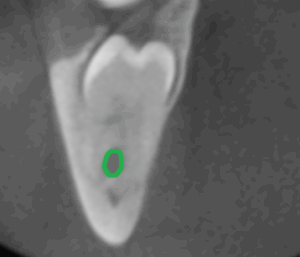

Weisheitszahn mit vorliegender Zyste – Auf dem ersten Röntgenbild liegt ein Weisheitszahn tief im Kiefer. Ausgehend vom Zahnsäckchen, das für die Zahnbildung erforderlich ist, hat sich eine Zyste an der Zahnkrone gebildet. Auf dem zweiten Röntgenbild ist zum besseren Verständnis die Zyste grün umrandet. Beim normalen Zahndurchbruch durch die Schleimhaut bildet sich das Zahnsäckchen zurück. Bei Zähnen, die im Kiefer verbleiben, kann sich, wie in diesem Fall, eine Zyste bilden und den Kiefer in seiner Stabilität schwächen. In diesen Fällen kann schon beim Kauen der Kiefer brechen. Eine rechtzeitige Entfernung solcher Zähne kann die genannten Risiken minimieren.